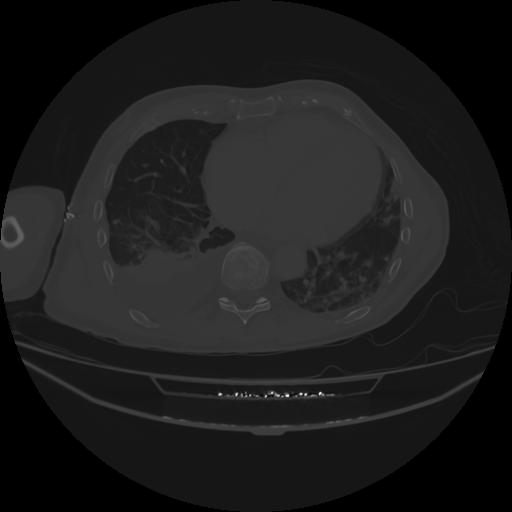

5 CUERPO,CE,Vol,1.0,CUERPO,,